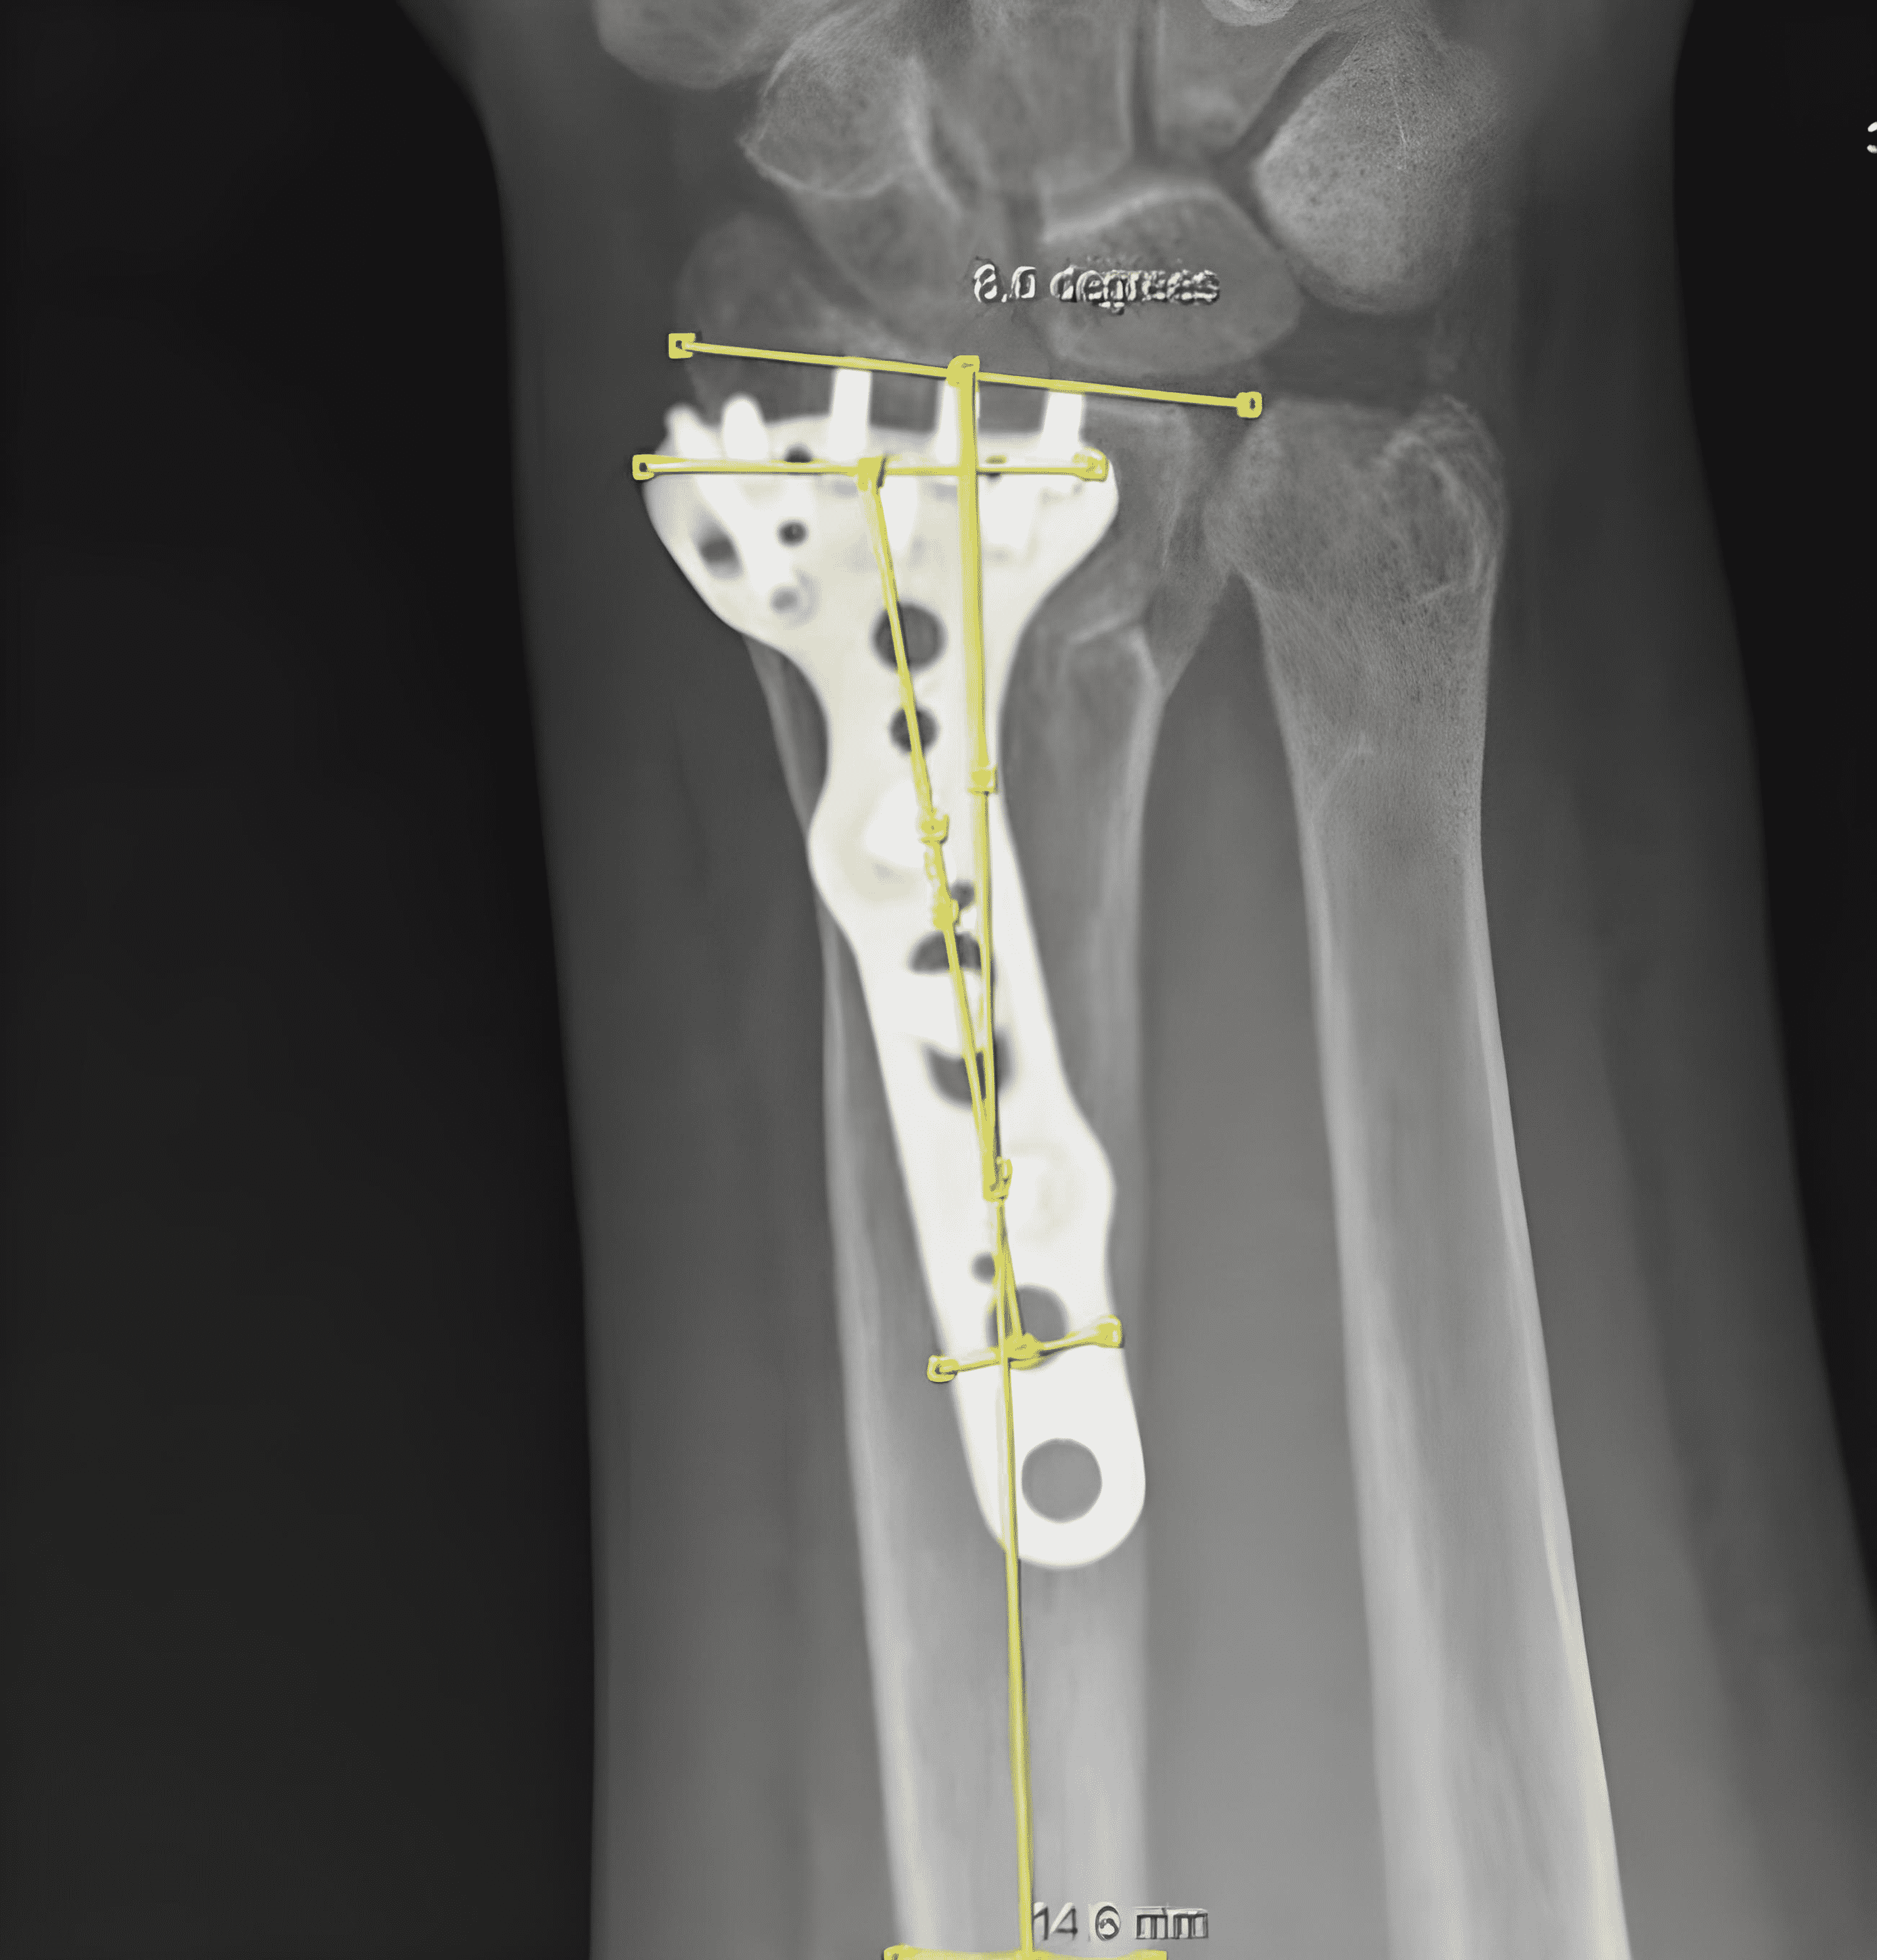

From www.researchgate.net

Anteriorposterior (AP) Xray of the left wrist showing volar plate Another Name For Volar Plate The volar plate helps maintain stability of the pipj in the anteroposterior plane and prevents pipj hyperextension. It happens when the finger is bent back or to the. A volar plate injury happens when your finger joint is bent too far backwards (hyperextension). The palmar ligament (also referred to as the palmar, or volar, plate) is a dense fibrocartilaginous thickening. Another Name For Volar Plate.